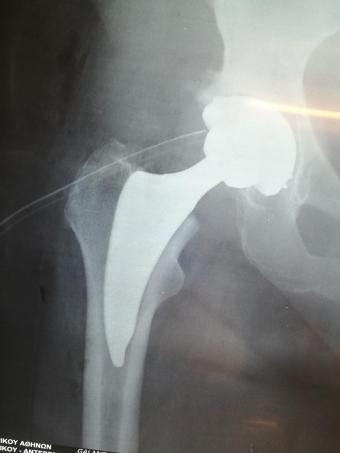

Стажування в приватній клініці у професора Христодулоса Афіни Греція листопад 2019

Компанія Lima надала стажування в ортопедичній приватній клініці місті Афіни Греція в листопаді 2019 року. Ендопротезування кульшового суглоба протезами компанії Lima малоінвазивним передньо-латеральний доступом у професора Христодулоса.